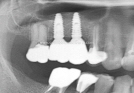

Clinical Cases

• Case1

• Case2

• Case3

• Case4

• Case5

• Case6

• Case7

• Case8

• Case9

• Case10